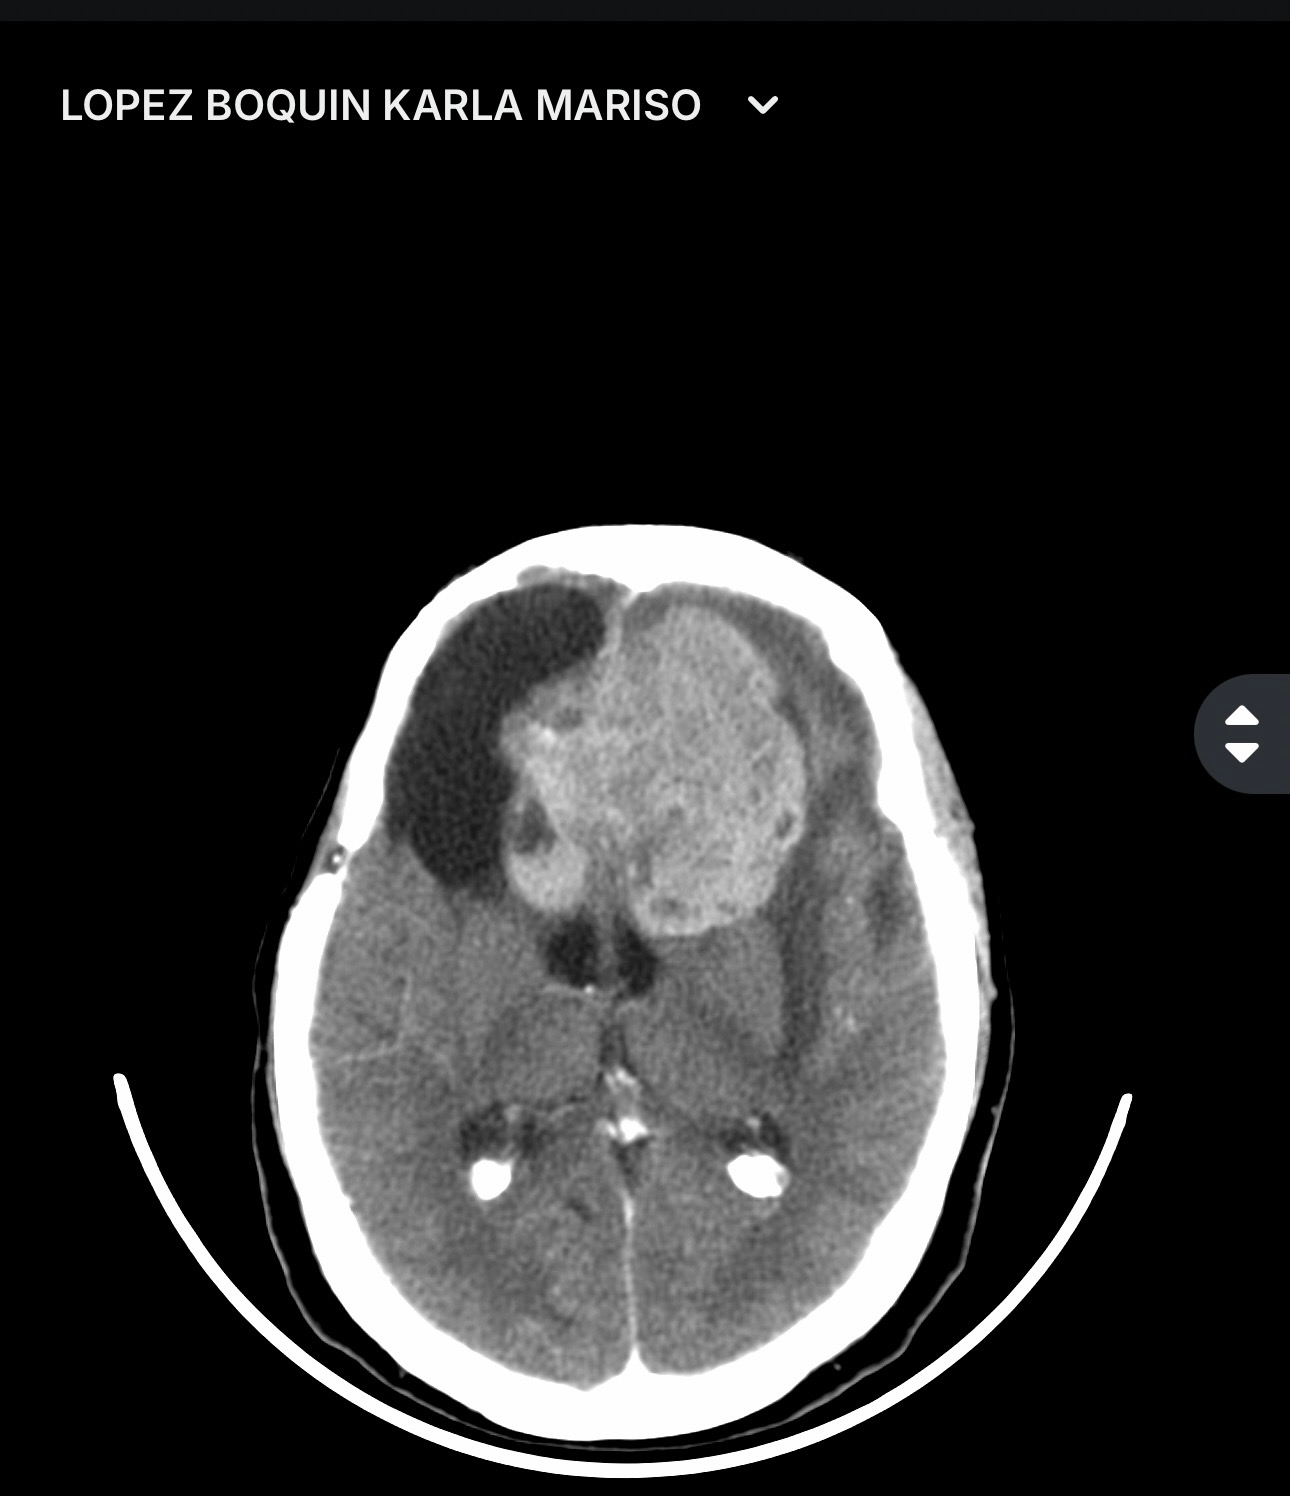

We are asking for help for Karla Lopez. She underwent her third neurosurgery for a brain and nasal tumor, as the tumor also invaded her nasal passages. Her children have covered all of her expenses for her last three surgeries. Unfortunately, she experienced post-surgical complications after her last surgery on May 12, 2025.

Her children are currently seeking help to cover the following procedures:

* External drainage

* Cranial valve installation

* Nasal tumor surgery

* Medical costs